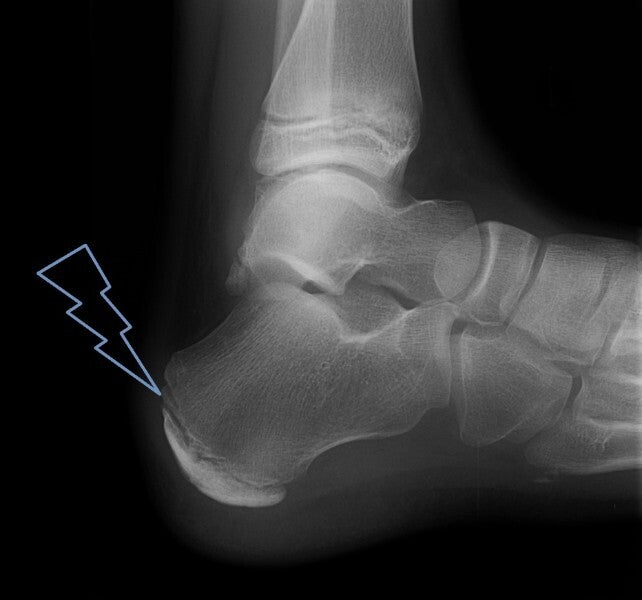

En cas de pathologies de croissance

Certaines affections, comme la Maladie de Sever (douleurs au talon chez les enfants de 8à 15 ans) ou les malpositions/malformations congénitales du pied, nécessitent un suivi spécialisé. Votre cabinet de podo-pédiatrie à L' Arbresle s'occupe du suivi et du traitement adapté à votre enfant.